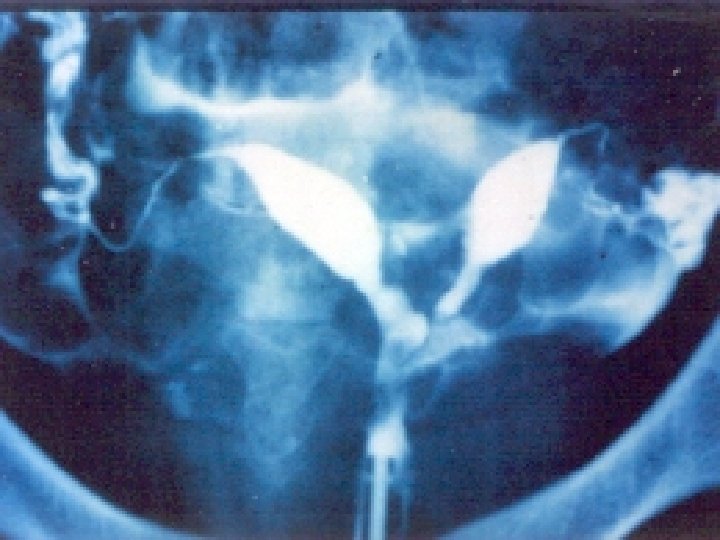

Obstructive Müllerian anomalies transverse vaginal septa and cervical agenesis and dysgenesis with or without obstruction. Imperforate hymen is embryologically not of mullerian origin although clinically have a similar presentation. Patients with this type of anomaly will usually presents with amenorrhea or pain due to accumulated menstrual flow.

b) Imperforate Hymen: The hymen represents the junction of the sinovaginal bulbs with the urogenital sinus; hence it is formed form the endoderm of the urogenital sinus epithelium. An imperforate hymen may be discovered at birth because of the presence of a supr More commonly however an imperforate hymen remains undetected until pubert